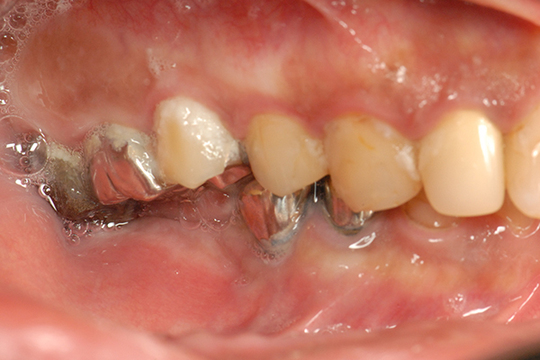

お口の中の虫歯の状態を表したものです。虫歯があるところには虫歯の初期~末期の4段階のイラストを使用して表します。虫歯の程度が軽ければ軽いほど簡単に修復することができます。進行が著しい場合には歯を残せない場合もあります。